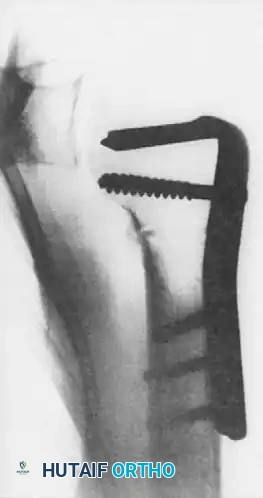

The osteotomy is rigidly fixed using an angled blade plate or a modern locking plate system.

Figures above illustrate the internally fixed humerus after transverse osteotomy and internal rotation of the humeral shaft using an angled plate construct. This effectively alters the articular arc, preventing the reverse Hill-Sachs lesion from engaging the posterior glenoid rim.